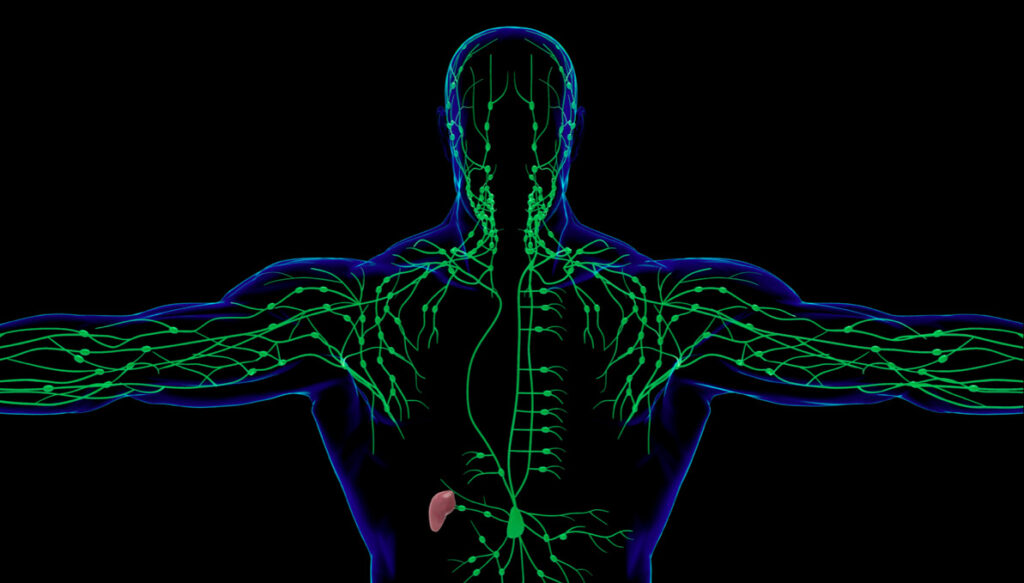

Linforisonanza (linfo-RM)

Che cos’è il linfedema? Il linfedema è una condizione caratterizzata da un accumulo di liquido linfatico in eccesso nelle parti del corpo, solitamente negli arti